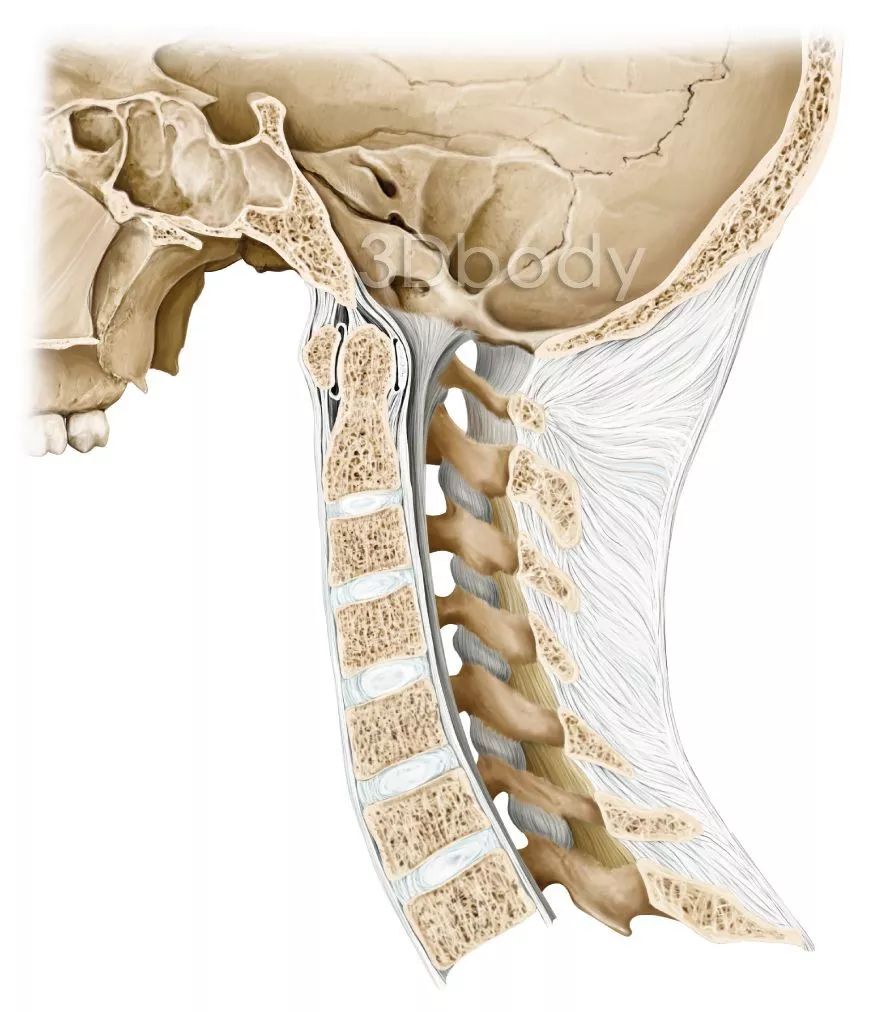

颈椎间盘突出的形成离不开力学结构的改变,即颈椎间盘受力不均匀,当颈椎有正常的生理曲度,椎间盘受力是均匀的,当颈椎没有生理曲度,颈椎间盘压力失去平衡,直颈使椎间盘前侧压力过大,髓核被挤压向后移动,压向薄弱的纤维环后部,后侧纤维环的撕裂,形成突出物,而直颈可以说是与生俱来的,这样十几年几十年颈椎节段间盘承受不正确的压力,你的间盘不突出都不可能。

答案是有的,颈椎没有生理曲度还会给椎间盘更大的冲击,举一个例子:当你轻轻的跳起、落地,如果落地的时候不屈膝,像冰棍一样的落地,你就会感受颈椎间盘承受的冲击了。颈椎的生理曲度可以缓冲60%-70%轴向冲击的力量,可以想象所有力量都集中在颈椎间盘上,没有生理曲度,甚至反弓,谁来保护你的颈椎椎间盘。